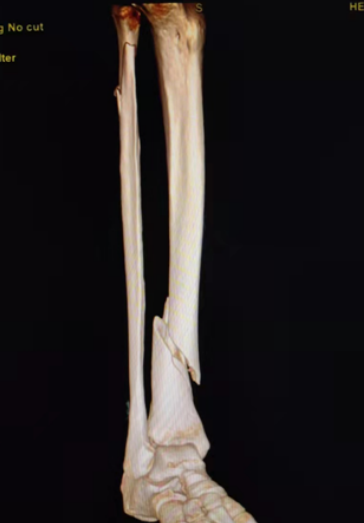

典型病例:女性,56歲,術(shù)前CT提示脛骨中下段骨折,移位明顯。

術(shù)后正側(cè)位片提示骨折達(dá)解剖復(fù)位,力線恢復(fù)正常。